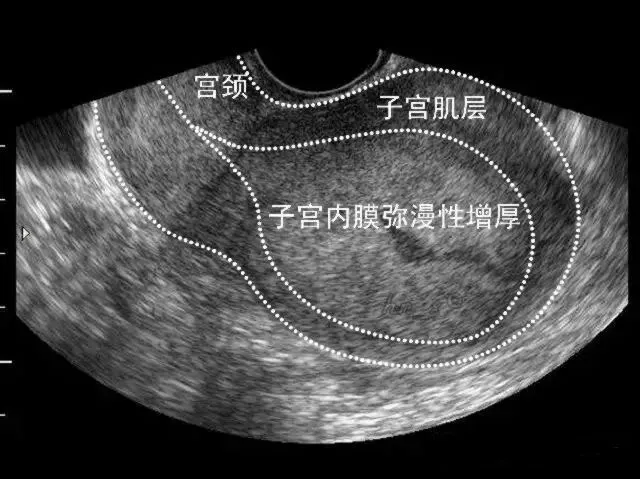

●二维超声表现:子宫内膜增厚、当病变累及肌层时局部内膜与肌层界限不清、早期子宫外形轮廓多无明显改变。

弥漫性子宫内膜癌声像